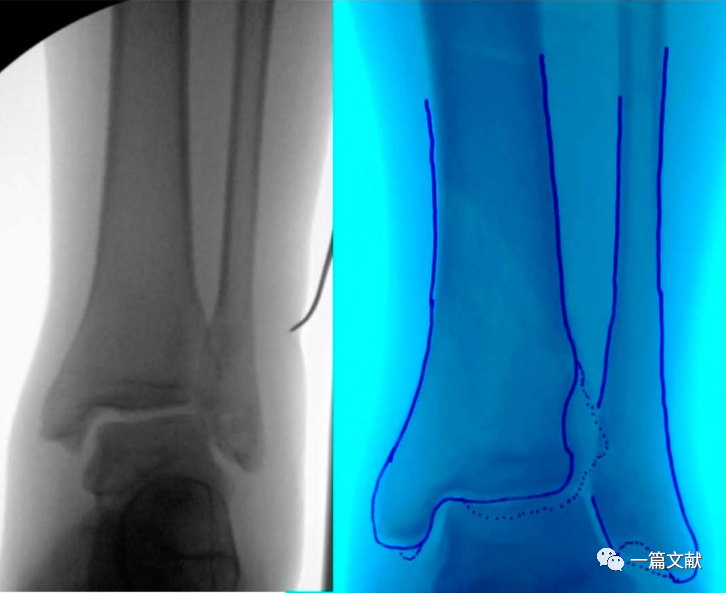

骨折畸形愈合的截骨矫形手术

此法可极大的简化截骨矫形手术过程,如下图: